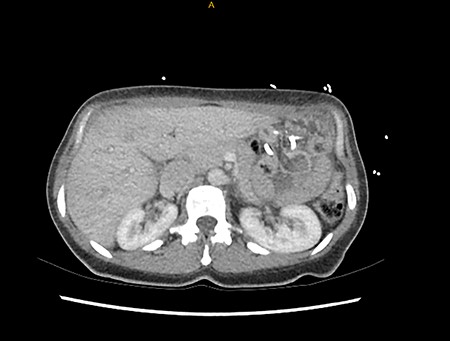

On presentation, she was not obstipated and did not have any per rectal bleeding. Her pain was coliky and unrelated to food. She was a non-smoker, denied any recent change in diet and was only a recreational drinker. She had no other significant past medical or surgical history. On examination, her observations were within normal limits, she had a tender epigastrium but otherwise, a benign examination. Computer tomography demonstrated an intussusception (Fig. 1).

Computer tomography findings of alimentary limb jejunal intussusception into the gastric pouch, through the MiniMizer gastric ring.